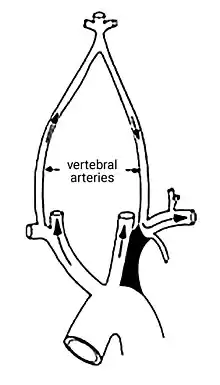

| The proximal part of left subclavian is blocked (shaded artery). This prevents antegrade ("forward") flow to the left arm and left vertebral. As a result, flow in the left vertebral is retrograde ("backwards") towards the left arm. Flow to the brain and circle of Willis is via antegrade right and left carotid and right vertebral arteries. | |

The blood vessels supplying the brain arise from the vertebral arteries and internal carotid arteries and are connected to one another by communicating vessels that form a circle (known as the circle of Willis).

Normally, blood flows from the aorta into the subclavian artery, and then some of that blood leaves via the vertebral artery to supply the brain.

In SSS a reduced quantity of blood flows through the proximal subclavian artery. As a result, blood travels up one of the other blood vessels to the brain (the other vertebral or the carotids), reaches the basilar artery or goes around the cerebral arterial circle and descends via the (contralateral) vertebral artery to the subclavian (with the proximal blockage) and feeds blood to the distal subclavian artery (which supplies the upper limb and shoulder).